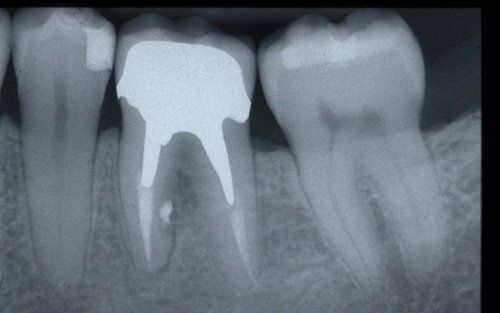

Endodontics, or root canal therapy, is that branch of dentistry that deals with the

devitalisation of teeth.

This treatment should be reserved for teeth that have irreversible pulp pathology (the nerve of the tooth) or an infection of the dental canals that has caused an abscess (acute apical periodontitis) or a granuloma (chronic apical periodontitis). While in the first two cases the tooth is very painful and the patient immediately seeks the dentist, the case of the chronic form is often silent, and therefore the patient may not notice anything for a medium to long period of time. In such conditions, it is only an X-ray image, taken during routine check-ups, that detects its presence. Root canal therapy can be completed by placing a latest-generation post inside the canal, as a means of retaining the material used for the reconstruction of the tooth. It will be up to the clinician to decide whether or not the restoration requires this additional anchoring system.